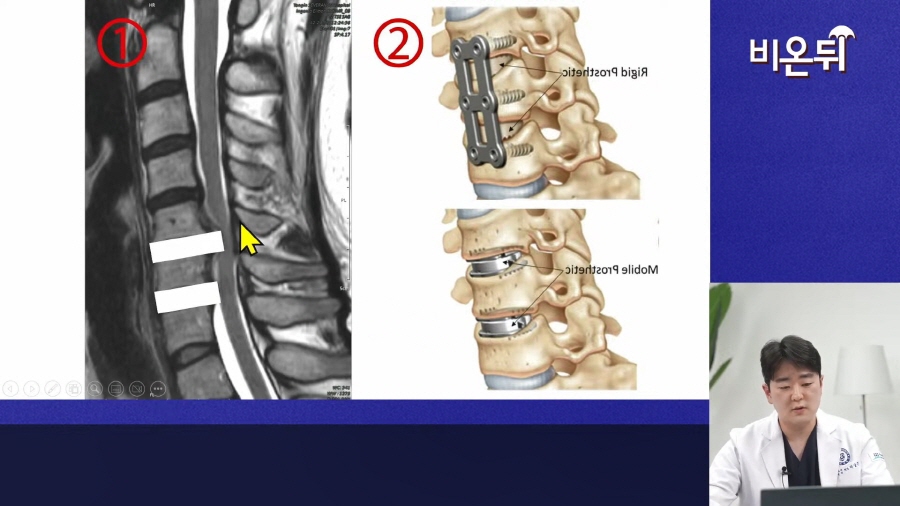

목디스크 수술 방법은 절개하는 방향에 따라 앞쪽이면 전방 수술, 뒤쪽이면 후방 수술로 나눕니다.

경추 1~7번 중 대부분 3~7번에서 문제가 나타나는데, 이 중 1~2마디에 문제가 있을 경우

전방 수술을 통해 신경을 누르는 골극이나 디스크를 직접적으로 제거한 후, 유합술이나 인공디스크 수술을 시행하게 됩니다.

이 때 유합술은 문제되는 디스크를 제거한 후, 목 뼈끼리 고정시켜 안정성을 회복하는 치료고

인공디스크는 제거한 디스크 대신 새로운 인공디스크를 넣어 경추 움직임을 보존하는 치료라고 보시면 되겠습니다.

하지만 3마디 이상의 디스크에 문제가 있을 때는 원인의 직접적인 제거보다는

신경 통로를 넓히고 확장해서 신경의 압박을 해소하기 위한 후방수술을 주로 시행하게 됩니다.